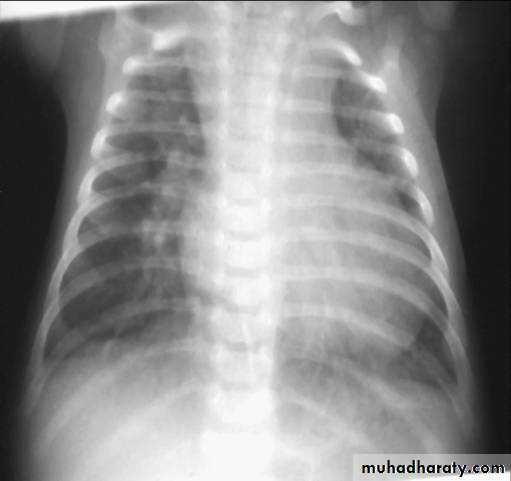

ATRIAL SEPTAL DEFECT (CONT.):

• Dx:• CXR:

• 1. Cardiomegaly of RV configuration. 2. Round apex peak.

• 3. Increase pulmonary marking

•